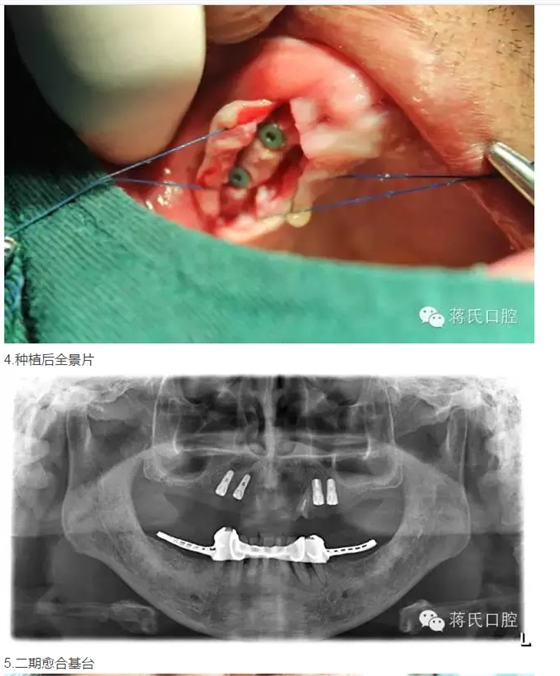

3兩側(cè)四五區(qū)種植共4顆

4活動義齒雙重冠修復(fù)

治療過程